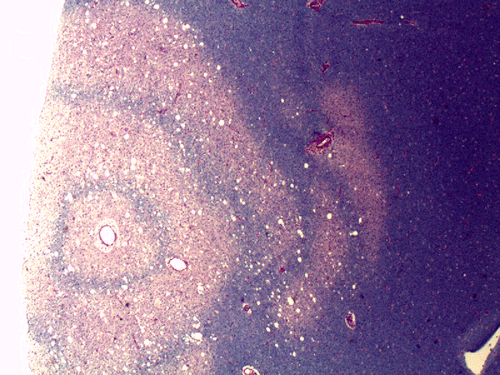

A left frontal lobe biopsy was performed and yield the following representative photomicrographs.

On CT scan, there is multiple hypodense white matter lesions that appear to spare a thin layer of subventricular white matter (Panel A). The T2-weighted images on MRI provides a more accurate estimation. The white matter in the occipital lobes is most affected (Panel A). There is extensive vacuolar changes in the white matter (Panel B and C) and there is a questionable increase in cellularity. In some of the thin walled blood vessels, there is a thin layer of perivascular lymphocytic infiltration which is free of atypia (Panel D, E, and F). The lymphocytes do not appear to extends into the parenchyma. On higher magnification, some large reactive astrocytes can be seen (Panel G). In a minority of areas, some concentric rings can be seen on hematoxylin-eosin stained sections (Panel H). These rings appear to be alternating rings of myelinated and demyelinated white matter and the vacuolar changes appear to be limited mainly to the concentric lesions. The adjacent myelinated areas are spared (Panel I). In some areas, the level of myelin loss appears to be proportional to the level of vacuolar changes (Panel J and K). On immunohistochemistry for glial fibrillary acidic protein (GFAP), the degree of gliosis is also more impressive in areas with more prominent vacuolar changes (Panel L and M). The vacuolar areas also appear to have a reduced density of axons (Panel N). Axonal spheroids are also present in these areas (Panel O). Although a prominent infiltration of foamy histiocytes is not noted on hematoxylin-eosin stains, immunohistochemistry for CD68 illustrated positive cells in a minority of demyelinated areas (Panel P). These cells lacks the foamy nature of macrophages and their morphology would suggest microglial cells. The reactive astrocytes are not immunoreactive for CD68 (Panel Q). Immunohistochemistry for T-cells (CD3) and B-cells (CD20) demonstrates only a thin rim of perivascular infiltration without significant extension into the surrounding parenchyma (Panel R, S, and T).